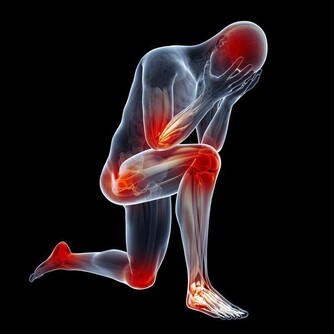

6.背部疼痛;